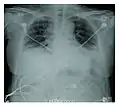

Rapid progression from initial symptoms to respiratory failure is a key feature. An X-ray that shows ARDS is necessary for diagnosis (fluid in the small air sacs (alveoli) in both lungs). In addition, a biopsy of the lung that shows organizing diffuse alveolar damage is required for diagnosis. This type of alveolar damage can be attributed to nonconcentrated and nonlocalized alveoli damage, marked alveolar septal edema with inflammatory cell infiltration, fibroblast proliferation, occasional hyaline membranes, and thickening of the alveolar walls. The septa are lined with atypical, hyperplastic type II pneumocytes, thus leading to the collapse of airspaces. Other diagnostic tests are useful in excluding other similar conditions, but history, X-ray, and biopsy are essential. These other tests may include basic blood work, blood cultures, and bronchoalveolar lavage.

Acute interstitial pneumonia showing a marked reduction in lung capacity Acute interstitial pneumonia showing a marked reduction in lung capacity